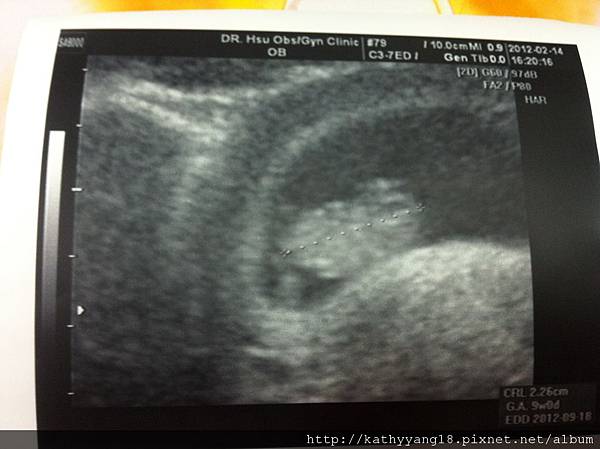

Hi!他坐著把手舉起來,嗨嗨~

這是3/2的超音波,當時11週多,

醫生說看起來很健康,